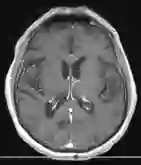

Standardized body region labelling of individual images provides data that can improve human and computer use of medical images. A CNN-based classifier was developed to identify body regions in CT and MRI. 17 CT (18 MRI) body regions covering the entire human body were defined for the classification task. Three retrospective databases were built for the AI model training, validation, and testing, with a balanced distribution of studies per body region. The test databases originated from a different healthcare network. Accuracy, recall and precision of the classifier was evaluated for patient age, patient gender, institution, scanner manufacturer, contrast, slice thickness, MRI sequence, and CT kernel. The data included a retrospective cohort of 2,934 anonymized CT cases (training: 1,804 studies, validation: 602 studies, test: 528 studies) and 3,185 anonymized MRI cases (training: 1,911 studies, validation: 636 studies, test: 638 studies). 27 institutions from primary care hospitals, community hospitals and imaging centers contributed to the test datasets. The data included cases of all genders in equal proportions and subjects aged from a few months old to +90 years old. An image-level prediction accuracy of 91.9% (90.2 - 92.1) for CT, and 94.2% (92.0 - 95.6) for MRI was achieved. The classification results were robust across all body regions and confounding factors. Due to limited data, performance results for subjects under 10 years-old could not be reliably evaluated. We show that deep learning models can classify CT and MRI images by body region including lower and upper extremities with high accuracy.

翻译:个人图像标准化体格标签提供了可以改进人体和计算机医疗图像使用的数据; 开发了一个CNN的分类器,以确定CT和MRI的人体区域; 为分类任务确定了覆盖整个人体的17个CT(18MRI)机构区域; 为AI模型培训、验证和测试建立了三个追溯数据库,每个机构区域的研究分布均衡; 测试数据库来自不同的保健网络; 对病人年龄、病人性别、机构、扫描机制造商、对比、切片厚度、MRI序列和CT内核的分类器进行了准确、回顾和精确性评价; 数据包括2 934个匿名CT案例的追溯组(培训:1 804项研究、验证:602项研究、测试:528项研究)和3 185个匿名MRI案例(培训:1 911项研究、验证:636项研究、测试:638项研究)。 初级护理医院、社区医院和成像中心27个机构对测试数据集进行了准确性评估; 数据包括:92%以上的性别比例和科目的追溯性案例; 95年的高级和90个高等级数据序列,显示为91至90区域。